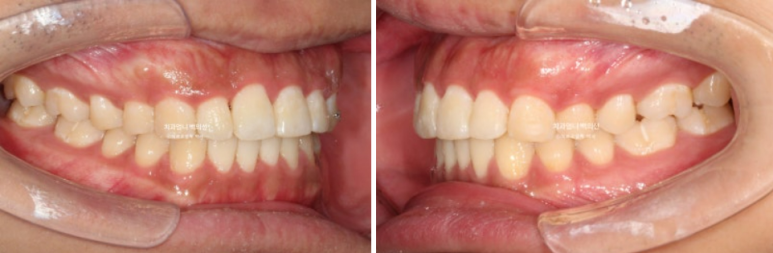

25.02~25.06

앞니가 기울어져 있고 중심선이 안 맞습니다.

어금니교합은 좋은 편입니다.

어금니 배열도 좋은 편이라 앞니 부분교정 권유드렸습니다.

이제 전 후 비교 보겠습니다.